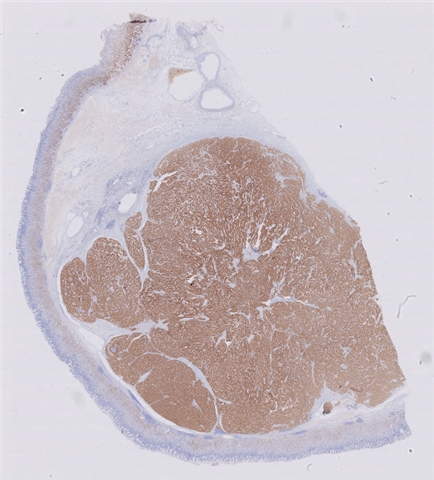

患者详情: 发现肛门肿物8月余,大便带血次数增多。外院病理检查:腺癌伴类癌分化。

大体所见: 肠管一段,直径3cm,长22cm,紧邻肛侧切缘、距另一侧切缘19cm处可见一菜花样肿物,大小6*6*5cm,切面灰白灰红色,质脆,侵及肠管全层,共取11块。

免疫组化: 蜡块一:CD20(-)、PAX-5(-)、CD3(-)、CD43(-)、EMA(局灶弱+)、CKL(-)、CK8/18(+)、CgA(-)、syn(+)、CD56(+) 蜡块二:GST-π(+/-)、TOPOII(+)、PGp(3+)、EGFR(-)、VEGF(+/-)、P53(小于3%+)、CERbB-2(-)